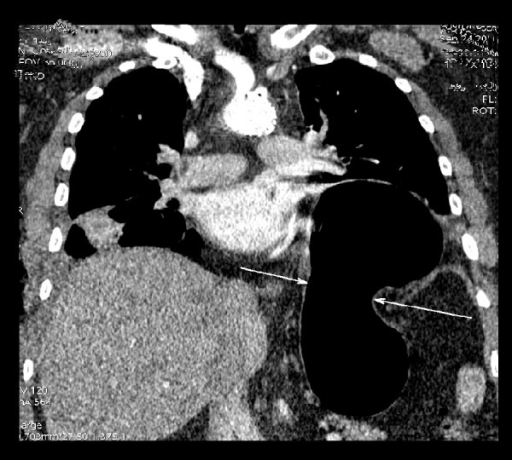

The Role of Computed Tomography in the Diagnostics of Diaphragmatic Injury After Blunt Thoraco-Abdominal Trauma Polish Journal of Radiology

| actual | 21:27 17 mar 2021 | 512 × 460 (209 kB) | Rossdonaldson1 (discusión | contribs.) | The Role of Computed Tomography in the Diagnostics of Diaphragmatic Injury After Blunt Thoraco-Abdominal Trauma Polish Journal of Radiology |